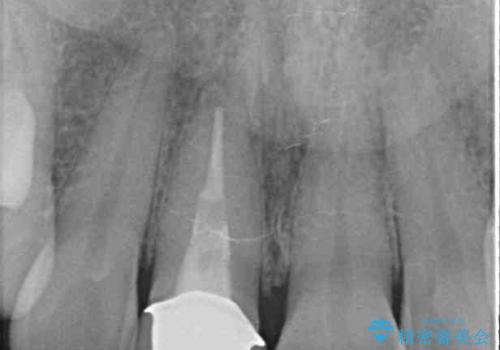

- 前歯のプラスチックが変色していることを気にして来院された患者様です。

反対側同名歯にセラミッククラウンが装着されていたため、そちらのクラウンと形態や色彩を揃えるようオーダーメイドタイプのオールセラミッククラウンにて補綴することとしました。